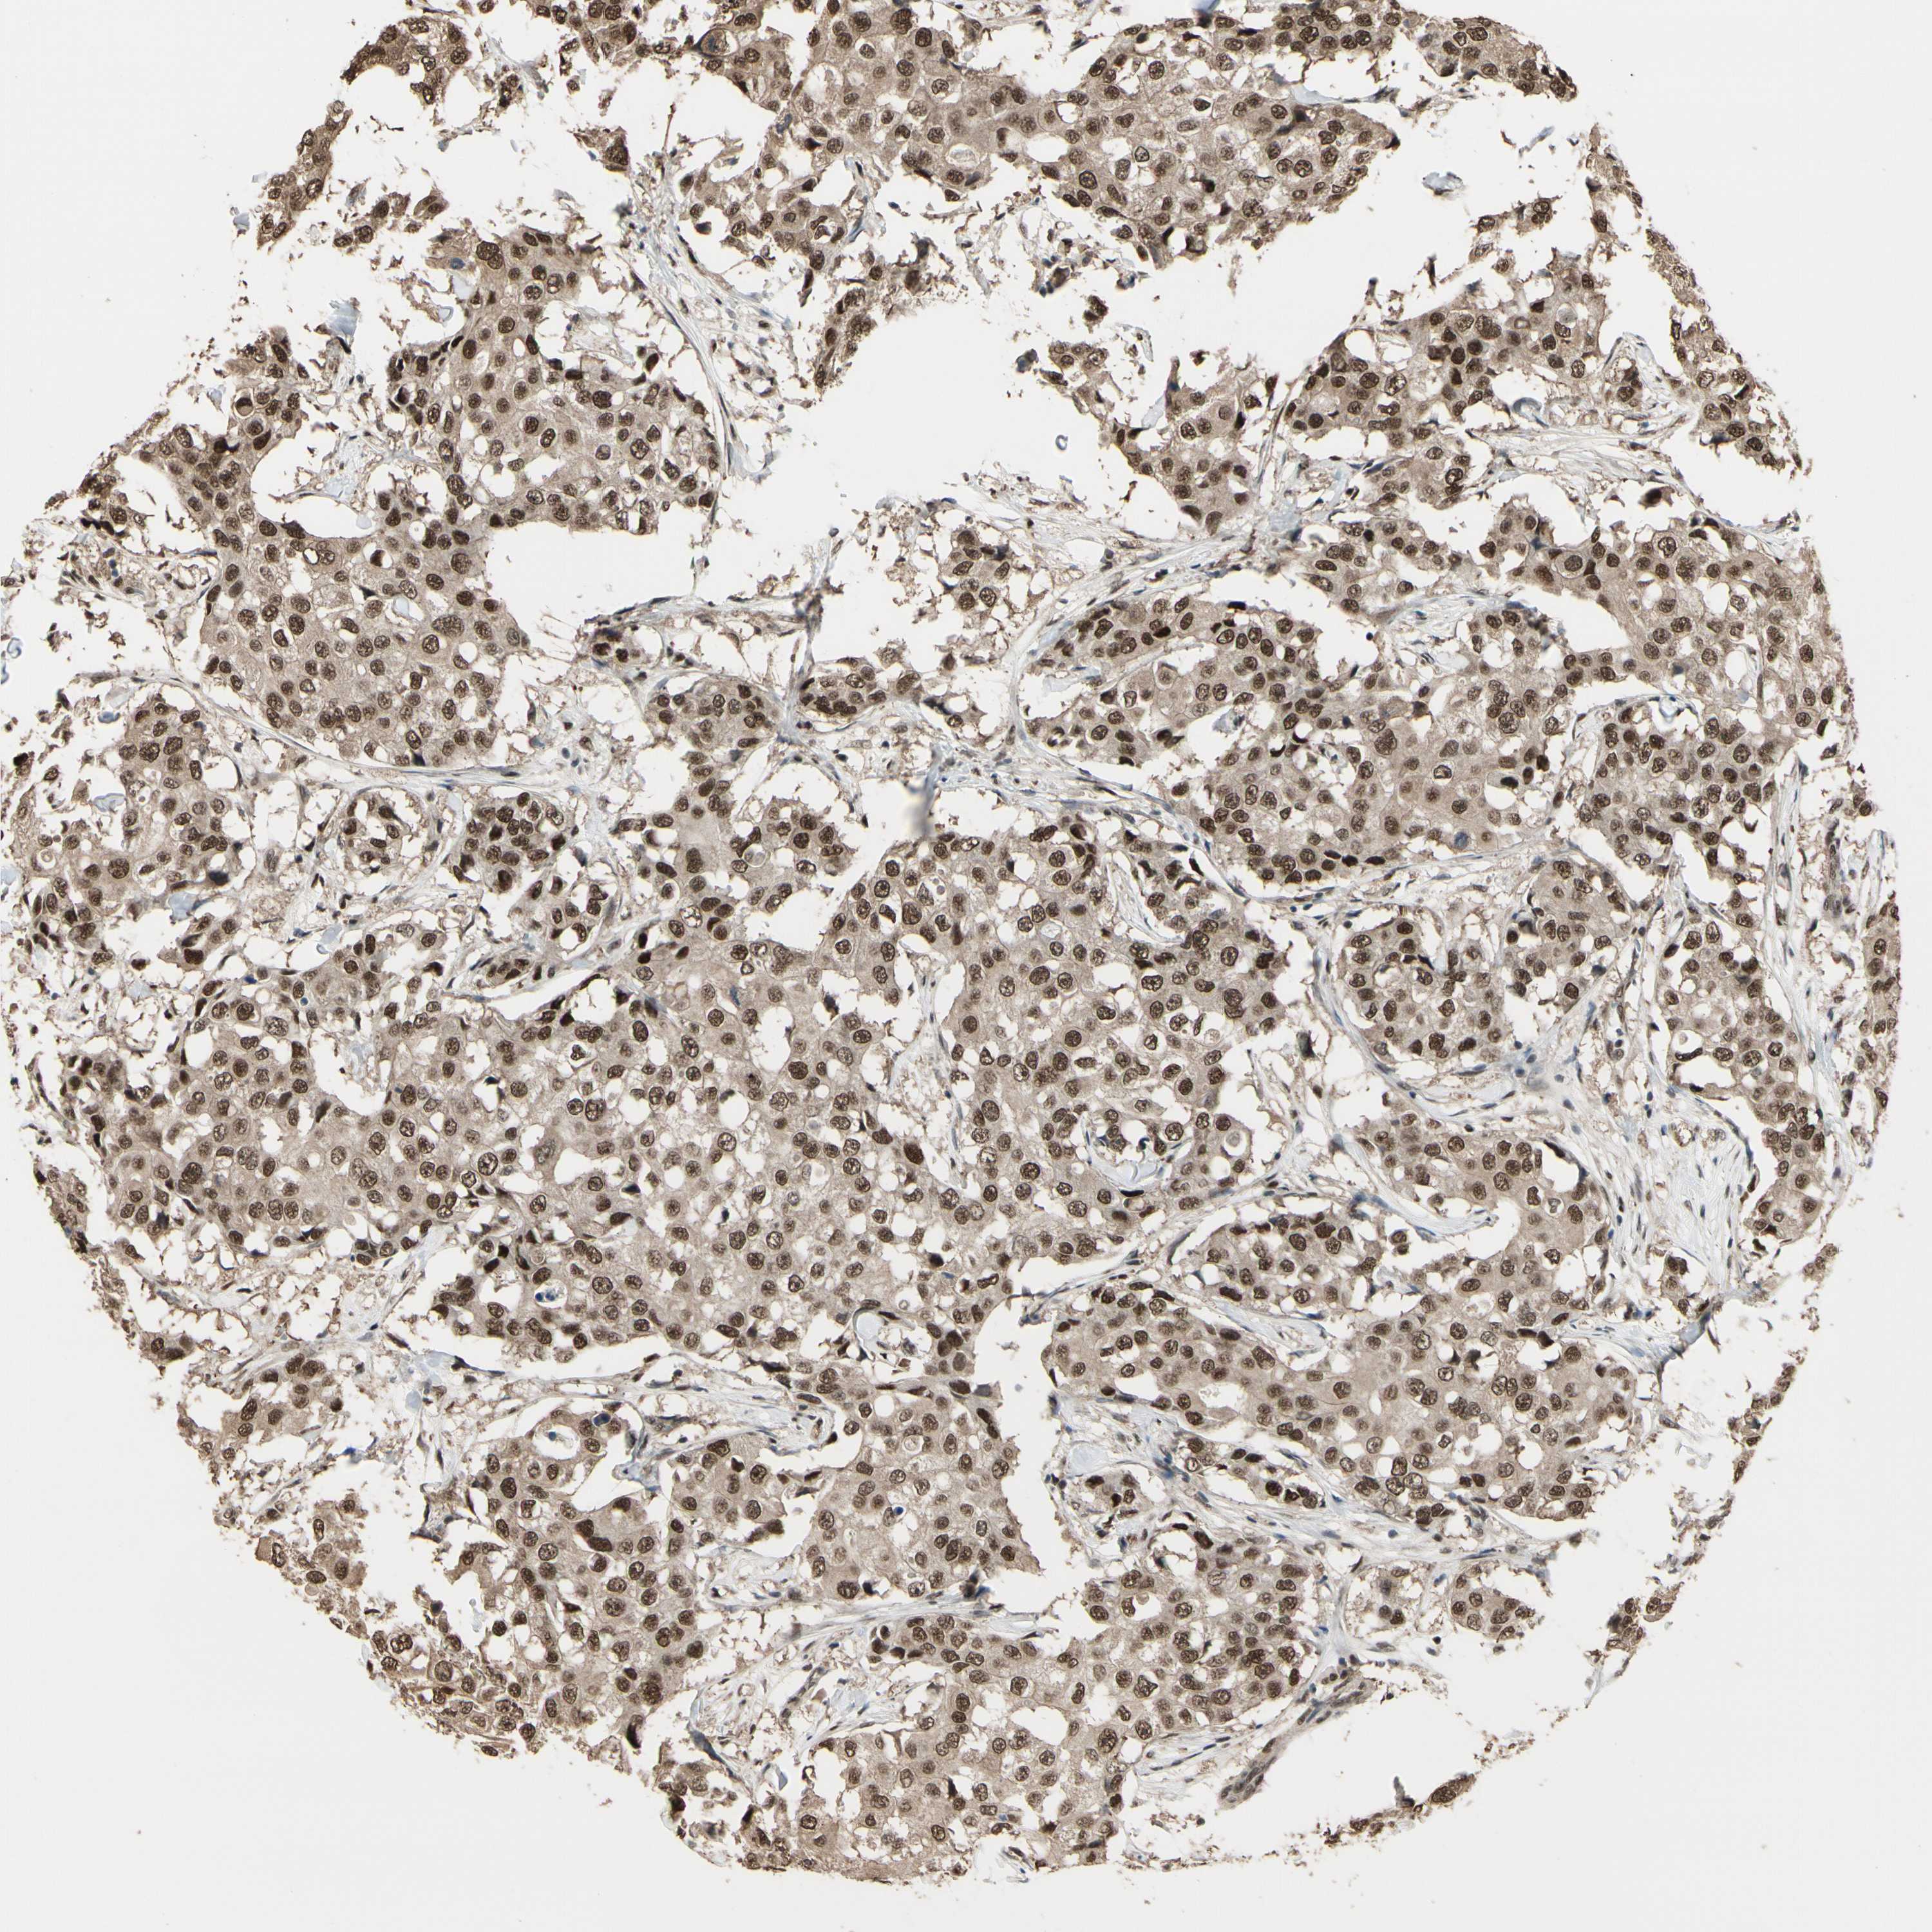

CANCER BREAST CANCER Show tissue menu

BRCA TCGA BRCA VALIDATION PROTEIN EXPRESSION

Breast cancer

Human cancer